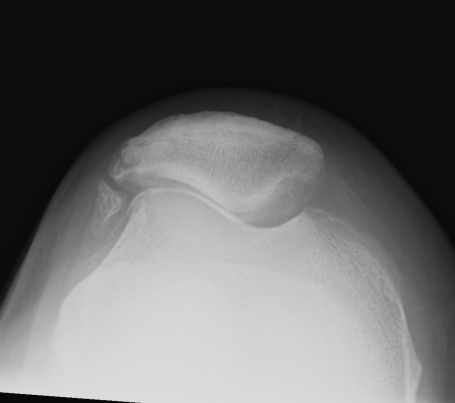

Abnormal / Crossover

- line of floor of trochlea crosses lateral lip of condyle

- indicates trochlea is deficient proximally